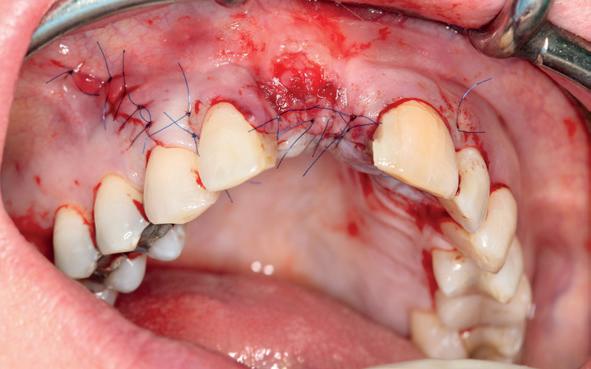

In het onderfront werd autoloog bot geoogst uit de kin regio ten behoeve van augmentatie (afbeelding

9. Botopbouw onderfront

9). In de bovenkaak werd bilateraal een sinuslift uitgevoerd. Aansluitend werden in beide kaakhelften implantaten geplaatst (afbeelding 10).